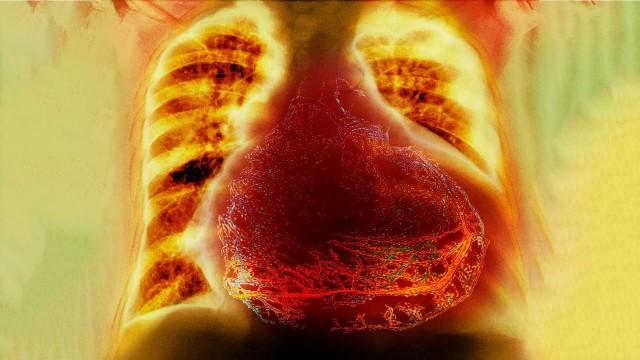

• S2020E04 A Grandpa Set His Clock Forward 1 Hour. This Is What Happened To His Heart.

☝️Presenting to the emergency room☝️ Please see references below in this description Peer review: Dr Rohin Francis (subscribe to his channel! @Medlife Crisis), Dr Boisey Barnes